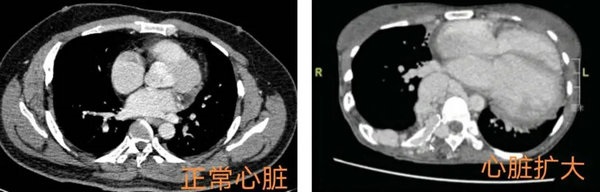

第四阶段:病情继续发展,回心血量增加,心脏负荷加重,可出现心力衰竭,心脏增大(图4),患者会表现为胸闷、气憋不适、下肢肿胀。特别是发生于躯干、邻近心脏周围头颈部、肱骨、肋骨、股骨等的动静脉畸形更容易导致心力衰竭。这将是未及时治疗后动静脉畸形发展的最后归宿。

▲ 图4